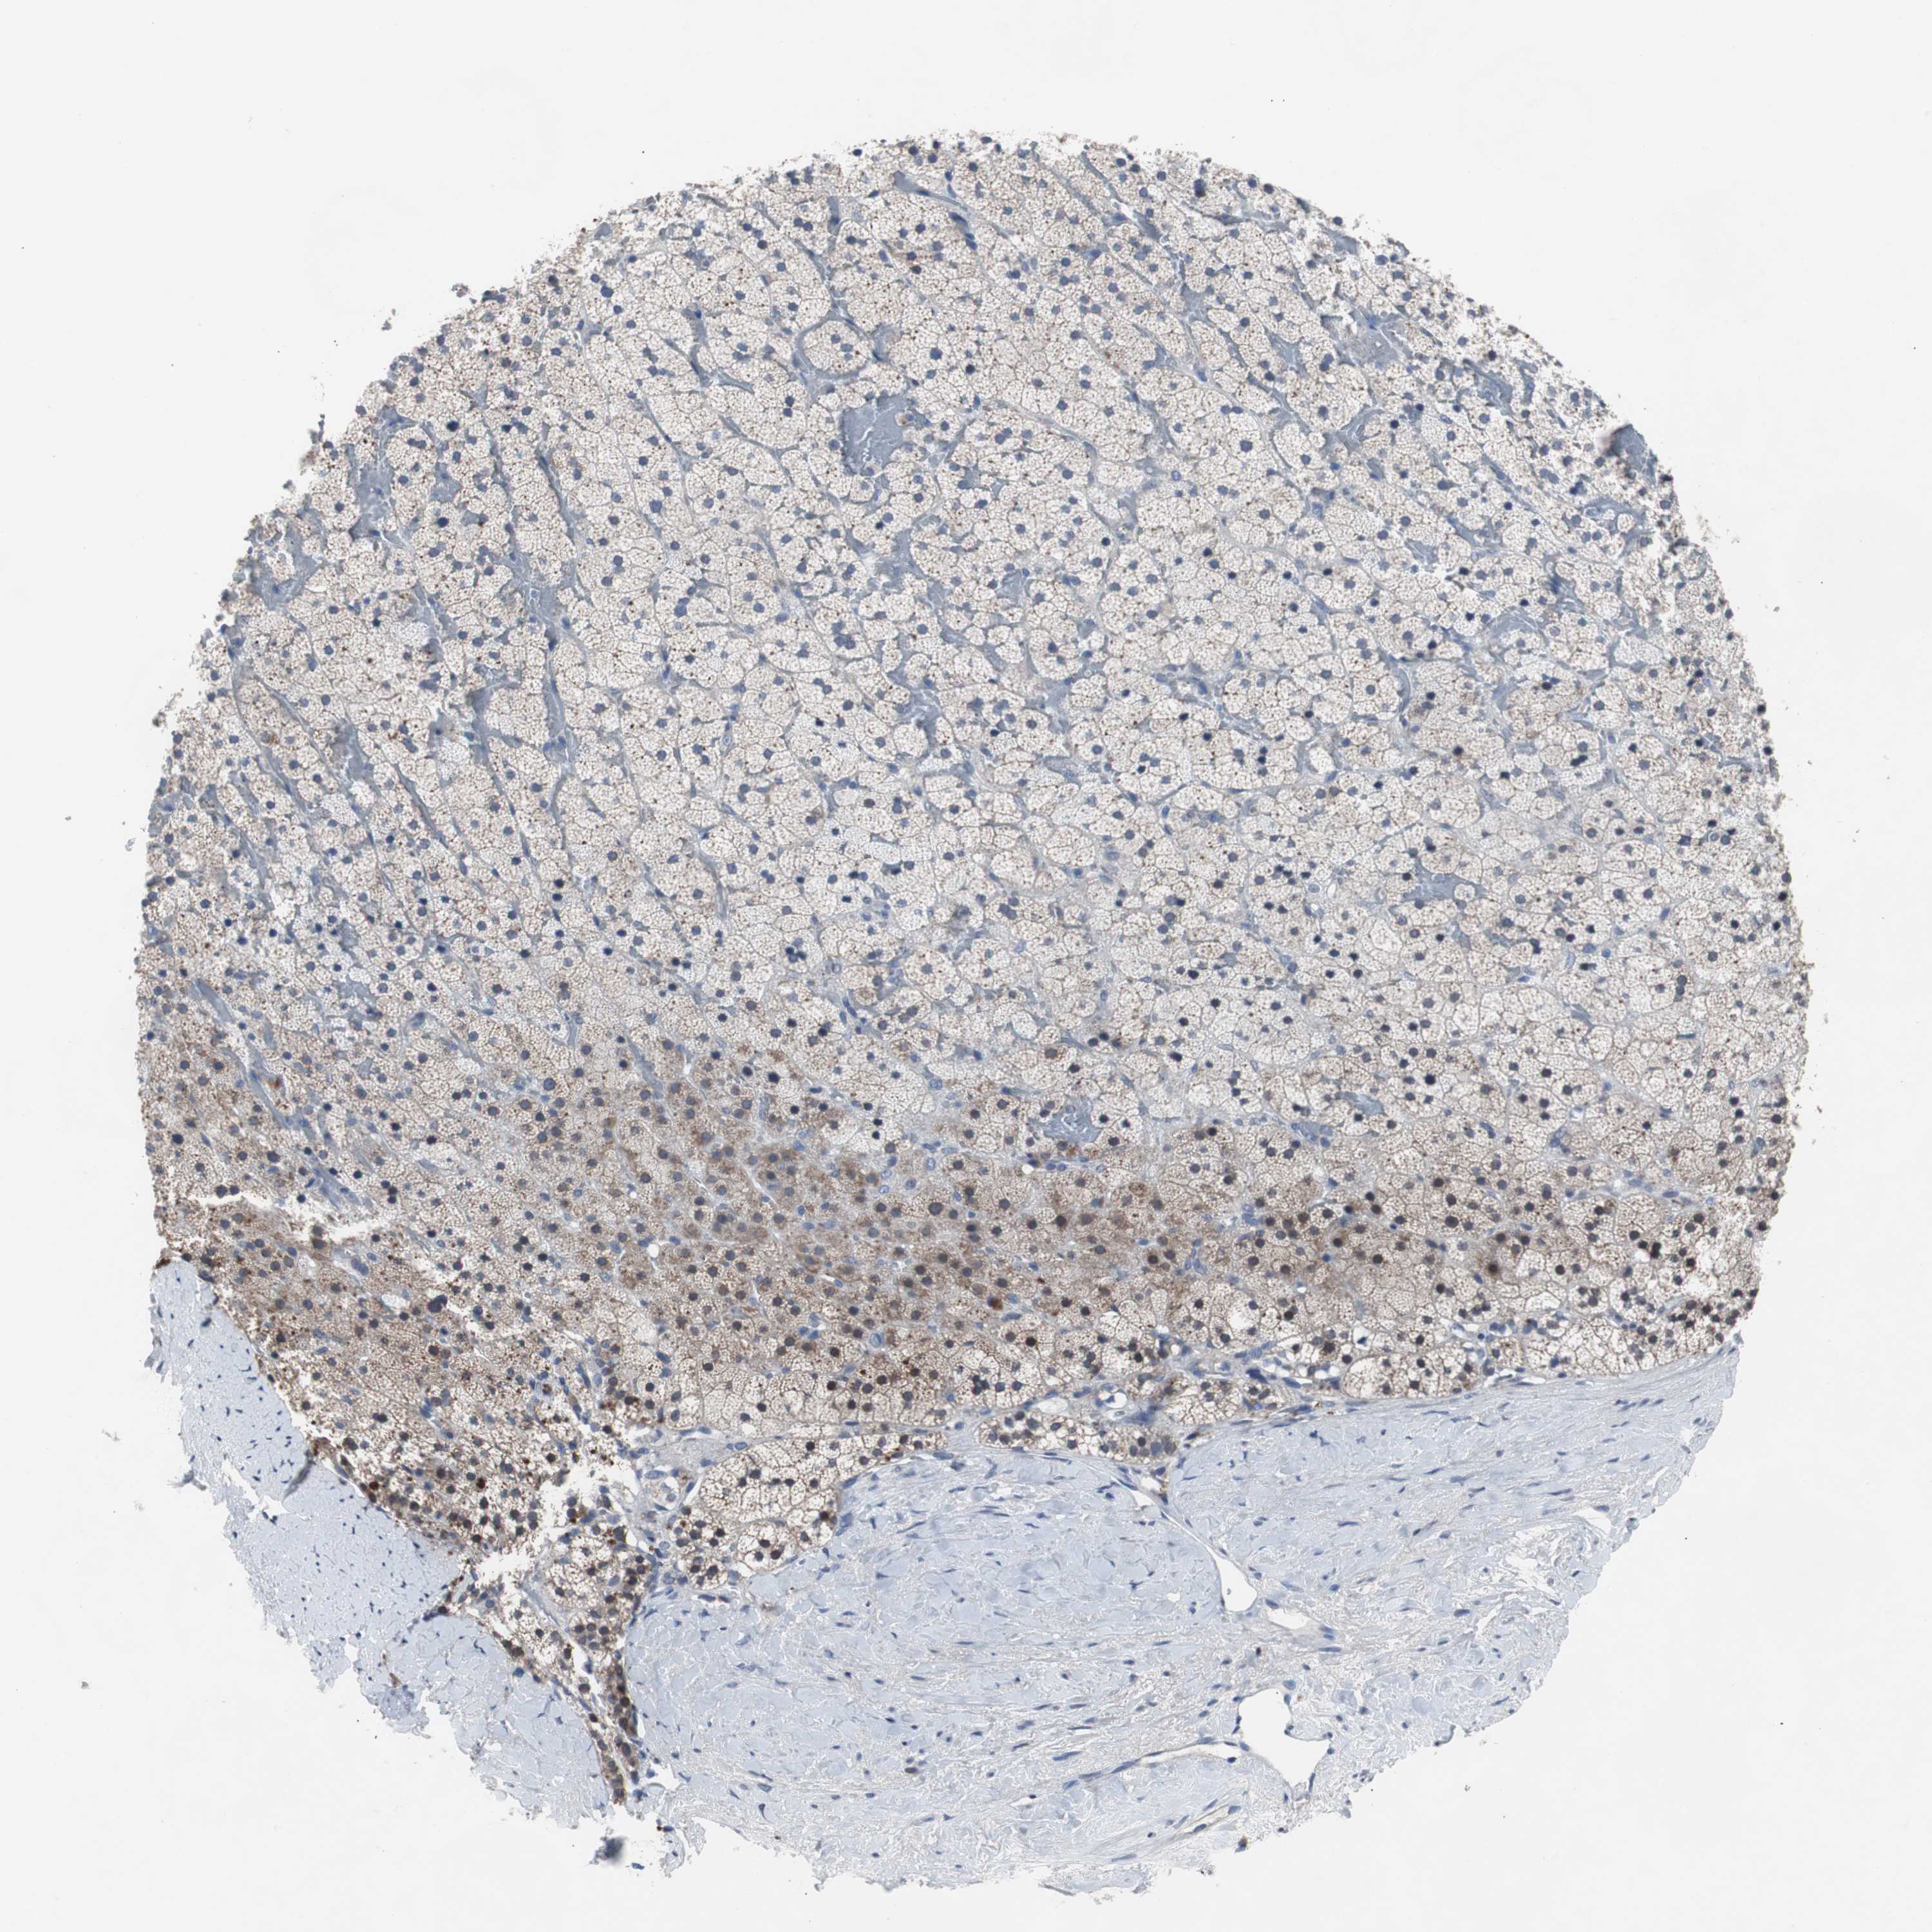

ADRENAL GLAND - Antibody stainingi

Antibody staining in the annotated cell types in the current human tissue is reported as not detected, low, medium, or high, based on conventional immunohistochemistry profiling in selected tissues. This score is based on the combination of the staining intensity and fraction of stained cells.

Each image is clickable and will lead to virtual microscopy that enables deeper exploration of all samples and also displays staining intensity scores, fraction scores and subcellular localization as well as patient and tissue information for each sample.

Antibody HPA006347

Glandular cells Medium